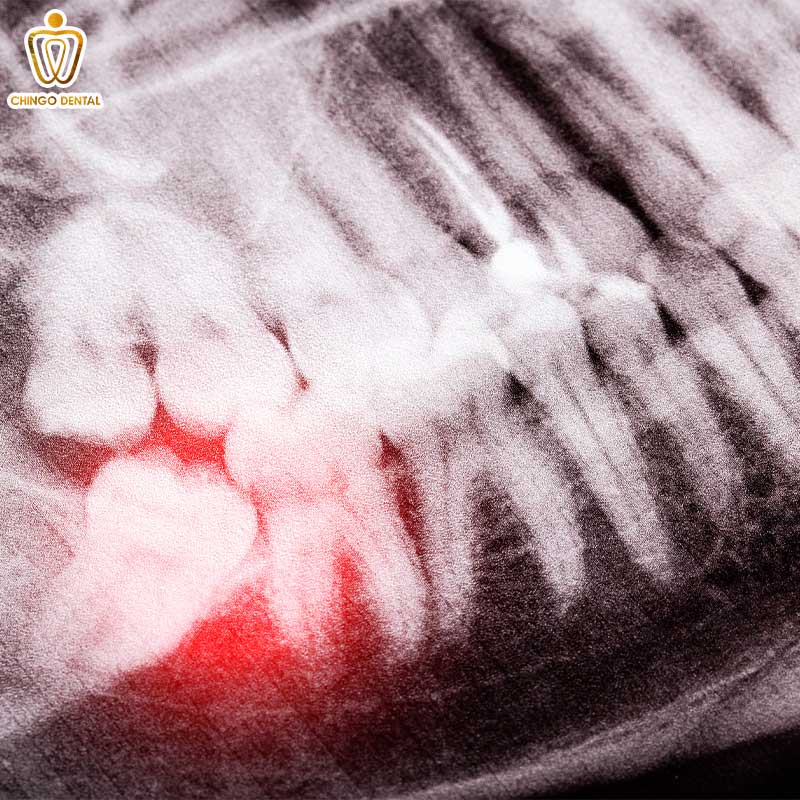

Áp xe răng hàm

Đây là tình trạng nhiễm trùng đã tạo thành mủ ở dưới chân răng hoặc kẽ nướu. Cảm giác đau răng hàm do áp xe thường kèm theo sự sưng tấy rõ rệt ở vùng má. Nhiều khách hàng phản hồi rằng họ thấy đau răng nổi hạch dưới hàm. Đó là phản ứng tự nhiên của cơ thể khi đang cố gắng chống lại ổ nhiễm trùng đang lan rộng.

Chụp X-quang phim toàn cảnh (Pano) để xem hướng mọc của răng khôn và có phương án nhổ bỏ nếu cần.

Đau kèm theo sưng mặt và sốt nhẹ

Đây là triệu chứng báo động đỏ. Khi vi khuẩn tấn công sâu tạo thành ổ mủ (áp xe) dưới chân răng, mặt bạn có thể bị lệch hẳn sang một bên, vùng da quanh đó nóng đỏ. Cảm giác đau lúc này rất nặng nề, chỉ cần chạm nhẹ lưỡi vào răng cũng thấy cực hình.

Tuyệt đối không tự ý chọc mủ hay đắp thuốc lá, hãy đến gặp bác sĩ ngay lập tức để được mở trống dẫn lưu mủ và dùng kháng sinh.

Nguy cơ mất răng vĩnh viễn và nhiễm trùng máu

Đây là lời cảnh báo nghiêm trọng nhất. Khi tình trạng viêm nhiễm đi sâu vào chóp răng tạo thành ổ áp xe, xương ổ răng sẽ bị phá hủy. Nếu bạn thấy đau răng nổi hạch dưới hàm kèm theo sưng mặt, đó là dấu hiệu vi khuẩn đang lan vào các mô mềm và máu. Nếu không được cấp cứu kịp thời tại các cơ sở chuyên khoa hoặc bệnh viện răng hàm mặt ở đâu uy tín, nhiễm trùng có thể lan vào xương hàm, gây hoại tử, thậm chí đe dọa đến tính mạng.